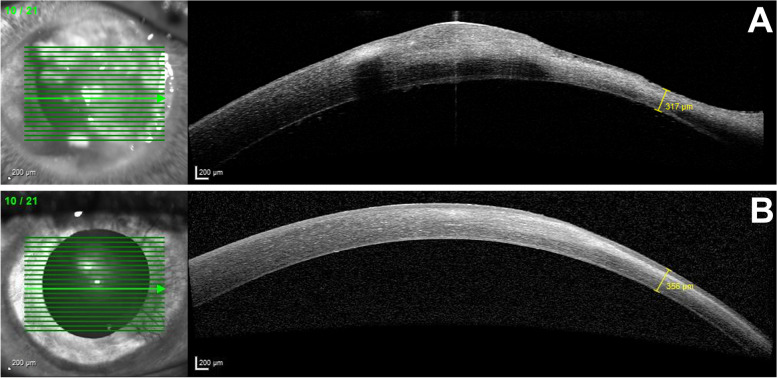

Fig. 2.

Anterior segment optical coherence tomography of the right eye: A) Day 8, thinnest corneal point 317 µm; B) after 8 months, corneal thickness 356 µm

After four and eight months, high irregular astigmatism (Fig. 3, follow-up after 8 months) and stromal scarring were evident (Fig. 1F, follow-up after 4 months; Fig. 2B, follow-up after 8 months). Visual acuity with the patient's old glasses was 0.2 (0.70 logMAR) and the intraocular pressure was 18 mmHg in the affected eye. At this point, further therapeutic options would have been a correction with glasses or contact lenses, a deep anterior lamellar keratoplasty (DALK), or a penetrating keratoplasty. In our opinion, the scar was too large for phototherapeutic keratectomy without sufficient residual thickness after laser ablation. Despite these findings and limitations, the patient was satisfied with his current state of his vision. At this time, he preferred not to undergo corneal transplant. He also decided not to get new glasses and stopped wearing contact lenses. After eight months, the patient presented with stable findings and visual acuity. The corneal thickness at the previous thinnest point was 356 µm (Fig. 2B). A follow-up visit is planned to reevaluate visual improvement for example by wearing contact lenses or by surgical options. The option of a corneal transplantation for visual improvement is still available in the future.